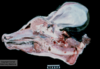

Name & describe the pathologic process.

Prosencephalic hypoplasia (AKA cerebral aplasia)

Absence of the cerebral hemispheres with preservation of at least some portion of the brainstem